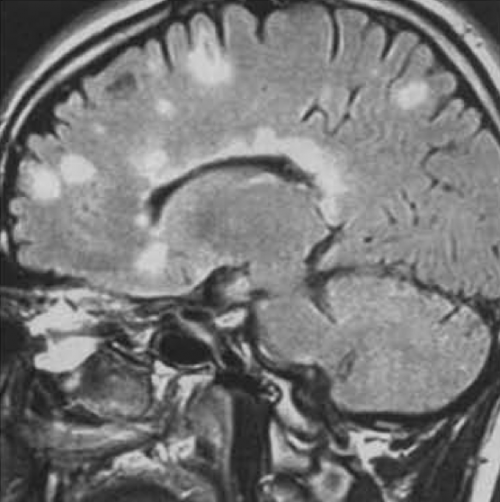

Sep Irm Normal Forum . IRM cérébrales et médullaires pathologiques dans le cas d'une SCLEROSE EN PLAQUE — Site des IRM signifie Imagerie par Résonance Magnétique. J'ai enfin pu le passer quand j'ai appris qu'il existait des IRM ouverts

Source: wpmarketmjd.pages.dev IRM cérébrales et médullaires pathologiques dans le cas d'une SCLEROSE EN PLAQUE — Site des , Parfois l'IRM cérébrale est normale car les plaques se sont formées uniquement au niveau de la moelle épinière. "Ma question est, peux ont avoir une sep même si les IRM apparaissent normal ?" Il est possible qu'il n'y ait pas de parallélisme entre les signes cliniques débutants et les résultats d'une IRM

Source: itiwebgwt.pages.dev IRM cérébrales et médullaires pathologiques dans le cas d'une SCLEROSE EN PLAQUE — Site des , Dans ces conditions, il est le plus souvent proposé. Parfois l'IRM cérébrale est normale car les plaques se sont formées uniquement au niveau de la moelle épinière.

Source: gsmdccryf.pages.dev IRM du cerveau normal (à gauche) et d'un cerveau avec sclérose en plaques aiguë (à droite).Sur , @Claudia.L J'ai fait ma dernière IRM le mois dernier, j'en fais tous les ans Dans ces conditions, il est le plus souvent proposé.